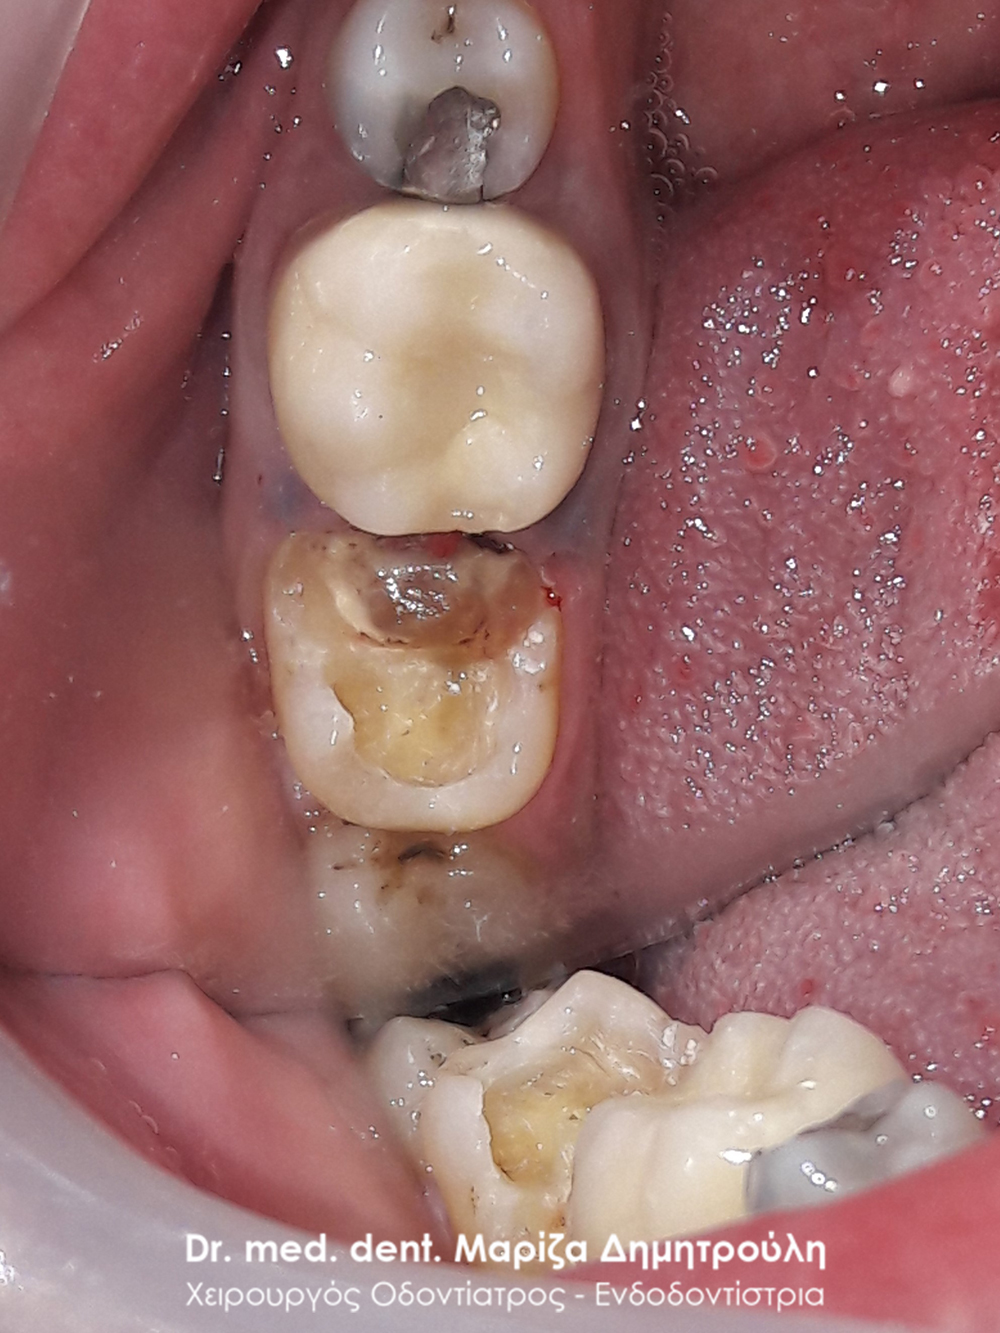

Στο παρόν περιστατικό απουσιάζει η αρχική εικόνα των δύο δοντιών πριν αρχίσει ο εκτροχισμός τους. Διαθέσιμες είναι μόνο η ενδιάμεση εικόνα που παρουσιάζει το εύρος του οδοντικού ελλείμματος στα δύο γομφίους της αριστερής πλευράς της άνω γνάθου και η τελική εικόνα αποκατάστασης των δύο δοντιών.

Η ασθενής αισθανόταν τις τελευταίες μέρες έναν ήπιο πόνο κατά τη μάσηση τροφών. Μετά την κλινική εξέταση του στόματος διαπιστώθηκε η ύπαρξη τερηδονικών κοιλοτήτων στους δύο άνω αριστερούς γομφίους. Αποφασίστηκε με τη συναίνεση της ασθενούς η αντικατάσταση των σφραγισμάτων. Στον πρώτο γομφίο διορθώθηκε μόνο η μισή έκταση του παλιού σφραγίσματος, καθώς κρίθηκε οτι δεν ήταν απαραίτητη η αφαίρεση ολόκληρου του παλιού σφραγίσματος.

ΠΡΙΝ

META